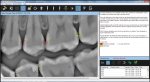

4. Logicon Caries Detector Software

Detect and treat early interproximal caries on permanent teeth with Logicon caries detector software.

carestreamdental.com

800-944-6365 • RSC #93